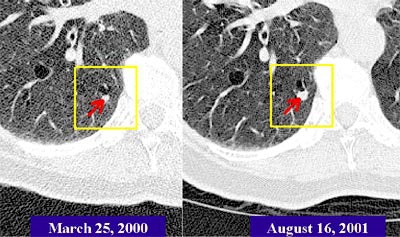

![]() |

| The Real-Time Automatic Matching System (RAM) is designed to automatically determine the corresponding location of nodules in another CT lung study. In the patient above, RAM located a nodule that had grown significantly over 17 months, even though radiation dose and other acquisition parameters had changed. Images courtesy of Siemens Corporate Research. |

"We see that (63.5%) of the (RAM) matches were exactly on the structure, and more than 90% were within 5 mm," she said. Computation time is very reasonable, she said; the computer performs the rough alignment of the entire study in about 15 seconds. Initial and follow-up scans of the same patient demonstrate the robustness of the system.

"Despite the fact that the nodule is much smaller in the previous study, despite the fact there is a quality difference between the two scans, RAM still managed to find it," Novak said. "This is a very reasonable system to use in the clinical setting because the computation time is so reasonable."